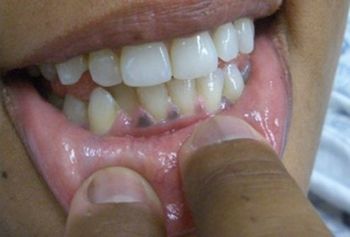

A 31-year-old woman presents with ongoing weakness and malaise and says her skin seems to be getting darker without exposure to the sun. Your Dx?

Weakness, nausea, abdominal pain, and a change in her skin color bring a nervous 31 y/o woman to see you. Your Dx?

She has had intermittent episodes of weakness and nausea for 6 months and is alarmed by the change in her skin color. What do her symptoms suggest to you?

Primary adrenal insufficiency or Addison’s disease, is the result of destruction of the adrenal cortex.